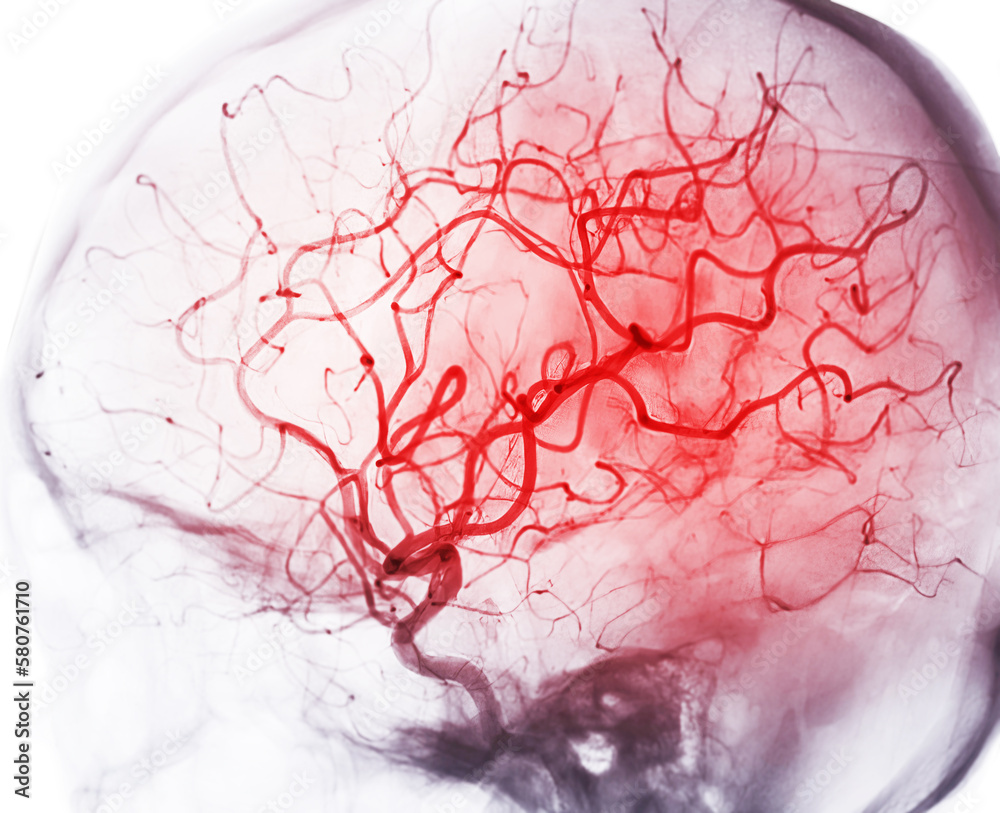

From stock.adobe.com

Cerebral angiography image from Fluoroscopy in intervention radiology Radiology Brain Areas it enables clinicians to focus on various parts of the brain and examine their anatomy and pathology, using different mri sequences,. Scroll through the images on the left. brain magnetic resonance imaging (mri) is a common medical imaging method that allows clinicians to examine the brain’s anatomy (1). We also discuss the causes for their. knowledge of. Radiology Brain Areas.

Cerebral arteriovenous malformation Radiology Case Radiology Brain Areas brain magnetic resonance imaging (mri) is a common medical imaging method that allows clinicians to examine the brain’s anatomy (1). knowledge of the vascular territories is important, because it enables you to recognize infarctions in arterial. brain mri with annotations of major structures. an understanding of brain arterial vascular territories is important in understanding stroke and. Radiology Brain Areas.